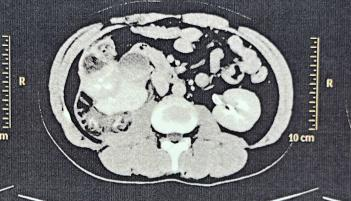

术前 CT 显示肾门结构紊乱不清

即便术前已经预估了手术难度较大,但术中的情况仍让我们非常吃惊,患肾肾门组织结构十分紊乱,毫无解剖层面,粘连十分严重,狭窄缺损的输尿管长达 3-5 cm 左右,无法直接与肾盂吻合,根据术中情况,与患者家属沟通后决定将输尿管与肾下盏吻合。